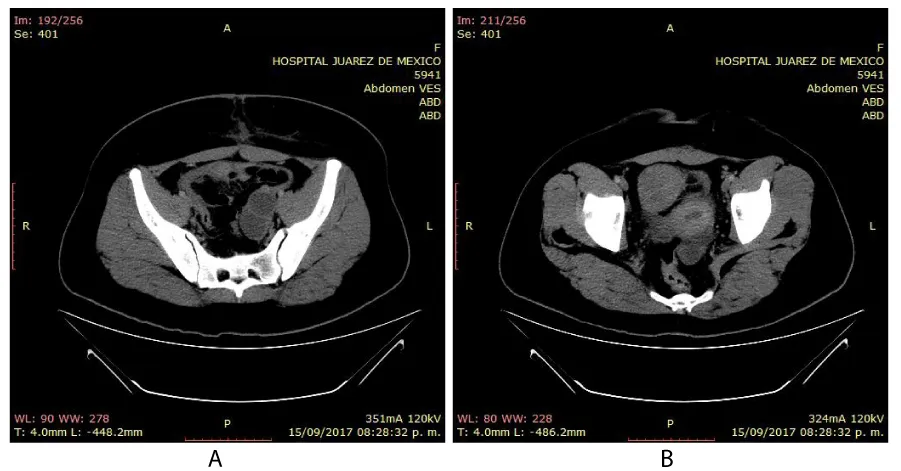

A 20-year-old married woman, with no history of pregnancy, who was admitted to the hospital for colicky abdominal pain in the right iliac fossa with radiation to the right iliac fossa from moderate to severe with Visual Analogue Scale with nausea and vomiting treated with analgesics presenting slight improvement; It is requested, quantification of the beta fraction of gonadotropin with figures of 112,337 mIU/mL and pelvic ultrasound with a report of a complex cyst of the right ovary without evidence of free fluid in the cul-de-sac; in relation to probable dysgerminoma or tumor of etiology to be determined; the hematic biometry with hemoglobin of 15.8 and hematocrit of 45, platelets of 313,000, leukocytes of 11,300 and 2 bands; reason for which she is referred to Hospital Juárez de México and once hospitalized; on August 18, 2017; she presents low-cost symptoms; and the studies are repeated quantification of beta fraction of Human Chorionic Gonadotropin (hGC) greater than 5,000, hemoglobin of 18 grams, hematocrit of 47%, leukocytes of 12,000, platelets of 367,000, lactic dehydrogenase of 473, direct bilirubin of 0.8 and the 2.3 total; normal liver transaminases; Ultrasound reports uterus in anteversion of 79x26x31mm, homogeneous myometrium, endometrial thickness of 7.9mm and right annex with lesion of 114 x83x79mm and total volume of 394cc, heterogeneous with linear images in its interior punctiform, the ultrasound diagnosis was, probable right annex teratoma tumor cystic.

On physical examination, the patient with generalized pallor of the skin and integuments, hypotensive, tachycardic, diaphoretic, without cardiorespiratory compromise, globose abdomen due to abundant adipose panniculus, perstalsis present, pain on palpation in the right iliac fossa on bimanual touch, the uterus is delimited 8x5 cm, right annex, 12x9 cm adnexal tumor, irregular, firm, pain on cervical mobilization, with spotting-shaped transvaginal hemorrhage, extremities without edema, normal tendon reflexes. According to the clinical presentation, imaging studies, on suspicion of ruling out ectopic pregnancy, an exploratory laparotomy was performed, with findings of the right annex of 20x15 cm adhered to the uterus and sigmoid rectum without evidence of hemoperitoneum and a right salpingo-oophorectomy was performed for probable right ectopic pregnancy with hematic loss due to the surgical procedure of 40cc and sent to pathology for definitive histopathological study, during follow-up a control gonadotropin quantification was requested with the last report of 1 103 918.7 mUI/mL. The histopathological results of the macroscopic surgical specimen were right salpingo-oophorectomy, with choriocarcinoma with extensive necrosis, 1 cm tumor extension to the ovarian surface not identified, lymphovascular invasion present and free surgical margins of the residual ovarian tumor with cystic follicles, Figure 1 and the report microscopic, Figures 2-4. A new hCG quantification is performed, negative head tomography and chest tomography with probable metastasis due to pulmonary nodule, in abdomen and pelvis, presence of peritoneal carcinomatosis, with free fluid and lumbar puncture reports negative for malignant cells and chemotherapy based on cisplatin and etoposide 5 sessions and the patient is disease-free after two years of follow-up.